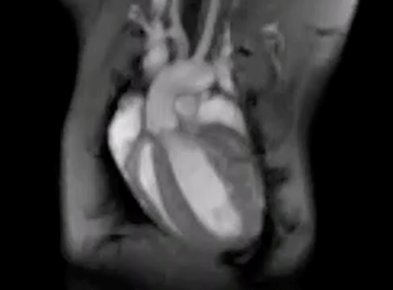

Ein Herz lässt sich reparieren

Bei Mäusen stellt eine Umstellung des Energiestoffwechsels die Herzfunktion nach einem Infarkt wieder her mehr